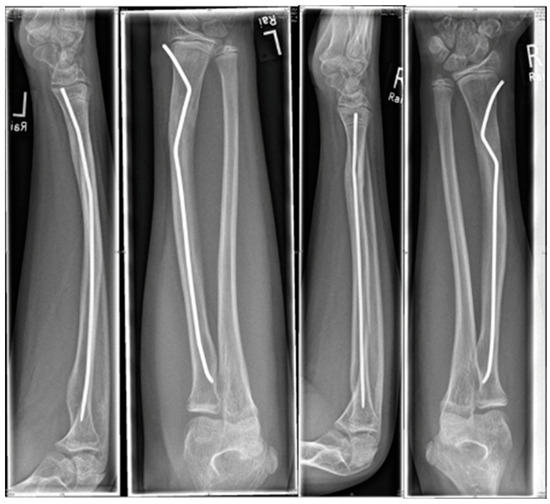

Scheme 3. 17-year-old boy.

The youngest patient was a two-year old boy, who presented with an unacceptable secondary displacement two weeks after trauma and, thus, this fracture became a rare indication for osteosynthesis in this age group (Scheme 2). The eldest was 17 years of age and did not show epiphyseal plates anymore (Scheme 3). This patient, however, suffered a new trauma 3 weeks later and underwent a redo-procedure in another hospital and, thus, was lost to follow-up. We even treated an open forearm fracture (on the ulnar side) with this technique (Scheme 4), leaving the fracture of the ulna to spontaneous healing and correction. This was because the risk of osteomyelitis due to intramedullary nailing of the open ulnar fracture to achieve a “nice X-ray” was estimated to be much higher than the risk of a remaining misalignment. Even a redo-procedure of a fracture that we had seen for the first time 4 weeks after an unacceptable K-wire osteosynthesis was successful, this time using a modification of the technique with a bend, rather than a kink distal to the fracture. Please note that the pre-bent nail pushed the 4-week-old fracture into a correct position without open reduction (Scheme 4). Last but not least, curiously, we saw one patient who suffered identical fractures in both arms, so we could perform the procedure twice in one operation (Scheme 5).